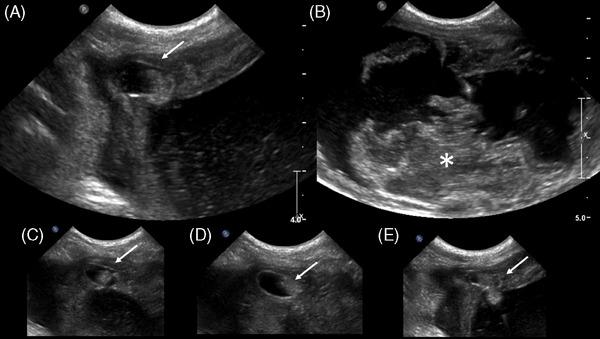

A young, intact, female, American Bulldog was presented for hemorrhagic vaginal discharge. Anemia, thrombocytopenia, leukocytosis with neutrophilia, azotemia, and electrolyte disturbances were detected in the bloodwork. A urachal diverticulum with concurrent uterine distention was identified by ultrasonography and CT. The diverticulum was excised in surgery, and an ovariohysterectomy was performed. Histopathological examination confirmed an abscessed bladder wall with concurrent pyometra.

一只年轻、未绝育的雌性美国斗牛犬因阴道出血性分泌物前来就诊。血液检查发现贫血、血小板减少、白细胞增多伴中性粒细胞增多、氮质血症和电解质紊乱。超声检查和CT检查发现一个脐尿管憩室并发子宫扩张。手术中切除了憩室,并进行了卵巢子宫切除术。组织病理学检查证实膀胱壁脓肿并发子宫蓄脓。